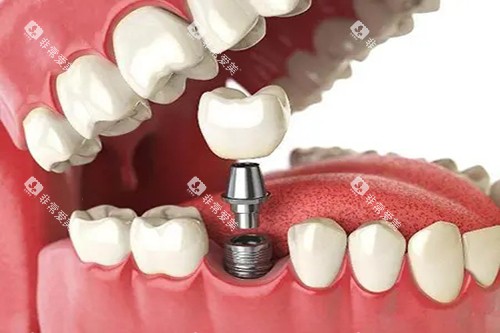

该门诊部的诊疗项目丰富多样,医生们的专长覆盖了口腔内科、口腔外科、牙齿正畸、牙齿美容等多个领域。

无论是日常的牙齿检查、洗牙,还是复杂的根管治疗和牙齿种植,患者都能在这里找到合适的医师进行针对性的医疗服务。

尤其在种牙和正畸方面,结果自然,能够满足患者对口腔健康和美观的需求。